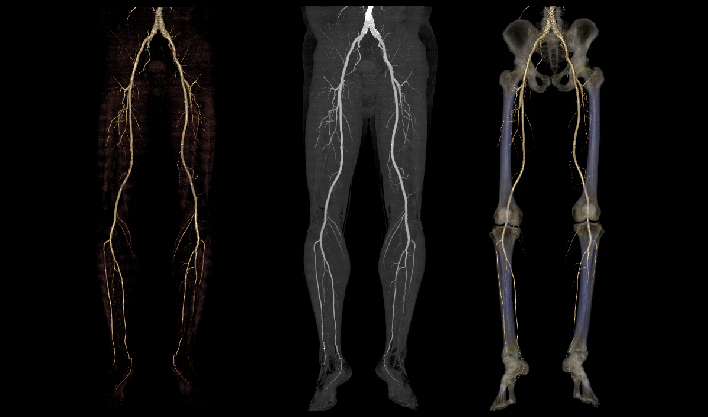

覆盖解剖、功能信息,“8”大临床场景赋能

快速扫描,精准“冻结”器官运动瞬间,高清呈现亚毫米结构,为心血管等系统疾病早期诊断和治疗提供黄金窗。